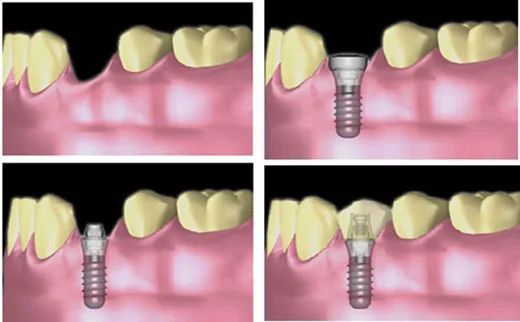

03 - 种植义齿

向左滑动查看种植修复,慎滑(图片来源于必应)

「适应症」:18岁以上、有一定的经济条件支持、缺牙区的骨头情况充足、全身条件良好、不愿意接受前两种修复方式、或者口内条件不足以行其它方式修复者。

「注意事项」:使用牙缝刷清洁邻面、定期随访;有牙周炎的患者需要积极治疗牙周炎,控制后方可接受种植手术;种植牙并不是一劳永逸的一种修复方式,维护不恰当也会出现相关问题,比如出血、松动、脱落。

「优点」:美观、舒适度、咀嚼效率高,不损伤旁边的健康牙齿,维护较好的情况下,10年使用寿命高达80-90%。

「缺点」:费用较贵,时间跨度需要半年以上;维护不好的情况下,存在种植失败及并发症的风险。